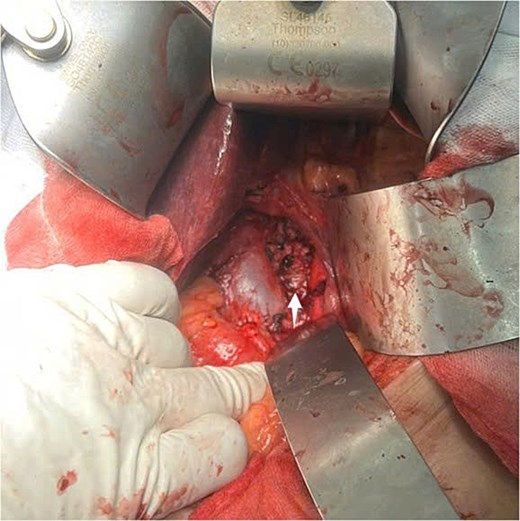

An exploratory surgery was performed, during which a well-encapsulated retroperitoneal mass was identified near the pancreas. The mass was completely removed with preservation of surrounding structures (Fig. 3). Gross examination showed a 60 × 45 × 35 mm yellow–gray encapsulated mass with scattered calcified foci (Fig. 4).

Intraoperative view of the retroperitoneal mass after complete surgical excision (indicated by arrow).